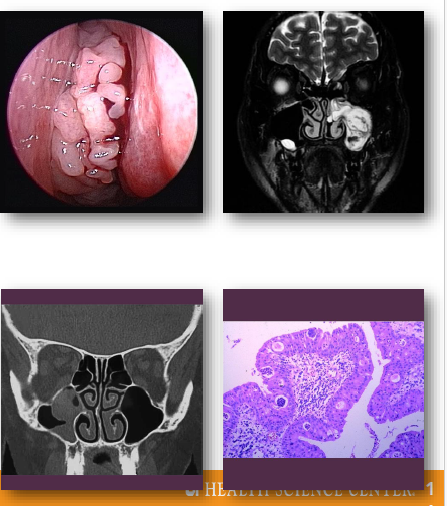

carcinoma of the maxillary sinus overview

•Malignant epithelial tumor of maxillary sinus

•Often squamous cell carcinoma histologically

•Associated with occupational and environmental exposures

•Frequently presents at advanced stage

•Close proximity to orbit and cranial structures

carcinoma of the maxillary sinus management and prognosis

• Requires combined surgical and oncologic therapy

• Radiation therapy commonly included in treatment

• Prognosis depends on stage at diagnosis

•Often poor due to delayed detection

Requires multidisciplinary management approach